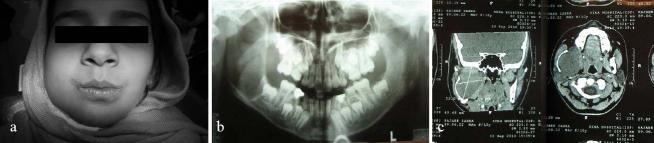

The neurilemmoma is a benign neoplasm of Schwann cell origin. One of the histopathologic subtypes of this tumor is ancient schwannoma which is characterized by degenerative alterations including cystic change, calcification, hemorrhage, and hyalinization.Intraosseous schwannomas especially ancient ones are rare tumors. Here we present a case of intraosseous ancient schwannoma in the lower jaw of an 11-year-old girl which caused a non-tender expansion. Radiographic examination showed a well-circumscribed, unilocular radiolucent lesion with thin sclerotic borders in the mandibular body and the ramus. Histopathologic examination of the incisional biopsy showed areas of typical Antoni A with verocay bodies and Antoni B that was strongly suggestive of a schwannoma. Complete excision of the lesion was done under general anesthesia. The histopathologic examination confirmed the primary diagnosis and also degenerative changes such as hyalinization and calcification. Based on these findings, the diagnosis of ancient schwannoma was made. No recurrence was observed in the follow-up examination after 3 months.

神经鞘瘤是一种起源于施万细胞的良性肿瘤。该肿瘤的组织病理学亚型之一是陈旧性神经鞘瘤,其特征为退行性改变,包括囊性变、钙化、出血和玻璃样变。骨内神经鞘瘤,尤其是陈旧性神经鞘瘤,是罕见的肿瘤。在此,我们报告一例发生于一名11岁女孩下颌骨的骨内陈旧性神经鞘瘤病例,该肿瘤导致无痛性膨隆。影像学检查显示下颌体和下颌支有一个边界清晰、单房性的透射性病变,边界有薄的硬化边。切开活检的组织病理学检查显示有典型的伴有Verocay小体的Antoni A区和Antoni B区,强烈提示为神经鞘瘤。在全身麻醉下对病变进行了完整切除。组织病理学检查证实了初步诊断,同时也发现了玻璃样变和钙化等退行性改变。基于这些发现,诊断为陈旧性神经鞘瘤。3个月后的随访检查未观察到复发。